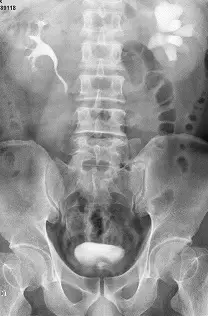

提供的圖片為靜脈注射對比劑後 15 分鐘的腹部前後位 X 光影像(KUB):

- 右側(正常):右側腎盂、腎盞及輸尿管清晰可見,管徑正常無擴張,且對比劑已順利排泄至膀胱,顯示右腎分泌與排泄功能良好。

- 左側(異常):左側腎臟呈現濃密的對比劑顯影,但其腎盞明顯擴張變鈍(Clubbed calyces),且腎盂顯著脹大,未見對比劑流入左側輸尿管。此為典型的左側重度腎盂積水(Severe hydronephrosis),強烈暗示左側存在尿路阻塞(如:輸尿管結石或腎盂輸尿管交界處阻塞 UPJ obstruction),導致排泄嚴重延遲。